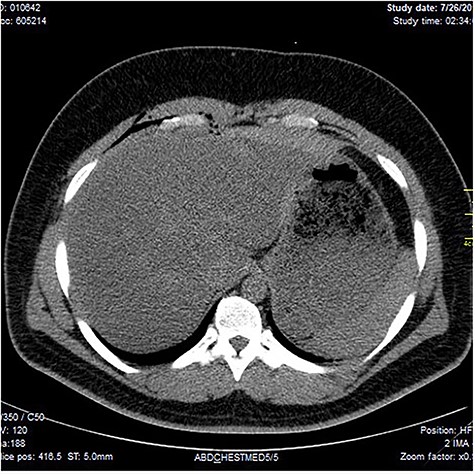

Chest X-ray was normal as shown in Fig. 1. Focused abdominal sonography for trauma (FAST) scan showed mild left perihepatic collection necessitating a thoracoabdominal computerized tomography (CT)-scan which showed external oblique muscle laceration with intermuscular air lucencies and grade 2 hepatic injury as shown in Figs 2–4. Other blood work-up were normal. No other injury was found on secondary survey. His wound was explored under local anaesthesia, primarily repaired, and he was discharged after 24 h of close observation.

Image shows lucent air densities tracking through the subcapsular haematoma in the left lobe of the liver anterior to the pylorus of the stomach.